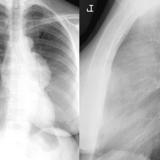

Case 8b Thymoma Lat

Date: 03/27/2009

Views: 14089